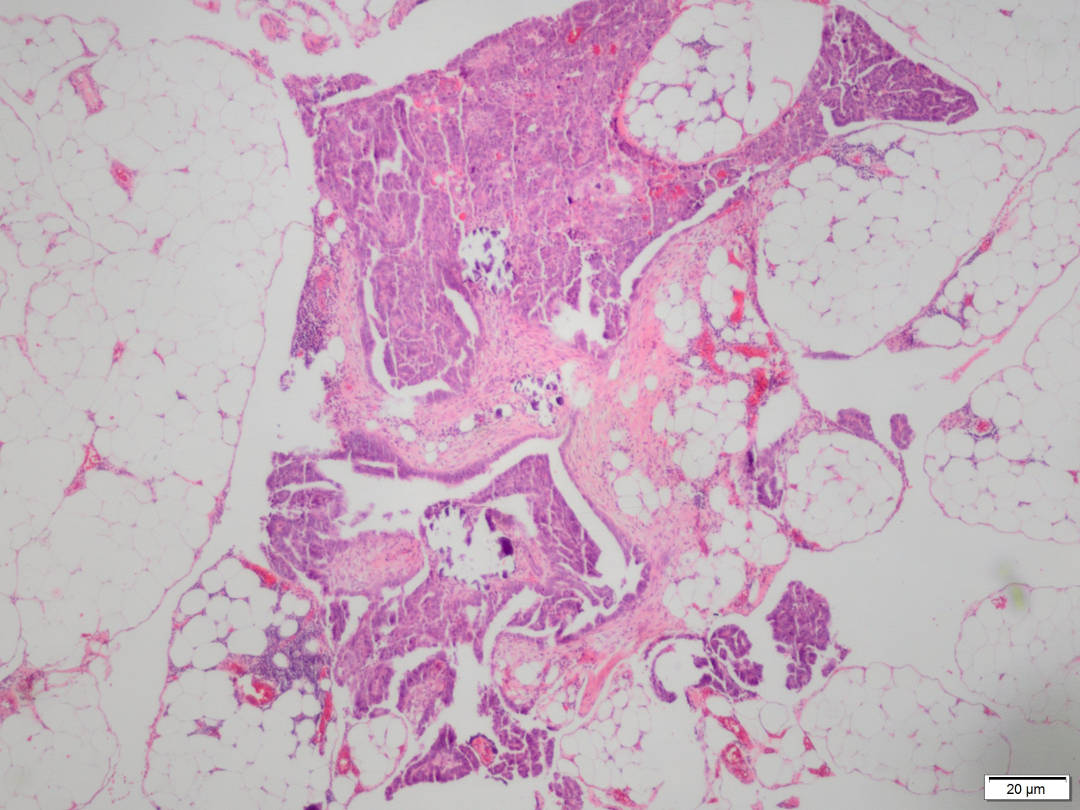

PATOLOGÍA pulmonar

Ofrecemos un servicio de diagnóstico integral que cubre todos los aspectos de la patología pulmonar, desde enfermedades neoplásicas y no neoplásicas, hasta las de la pleura y mediastino. Nuestros patológos emplean la gama completa de técnicas básicas y especializadas, para evaluar las biopsias y las resecciones de pulmones, pleura, timo y otras muestras de mediastino.